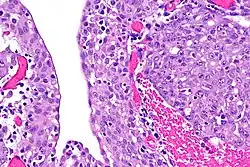

Renal medullary carcinoma (right of image), reactive urothelium and sickled red blood cells. H&E stain.

The finding that virtually all people affected by renal medullary carcinoma carry at least one copy of the HbS mutation suggests that sickle cell trait somehow predisposes to this type of cancer.[5] The precise mechanism is unknown, but red blood cells with a sickle cell configuration have been identified in pathology specimens.[2]

The diagnosis of renal medullary carcinoma is typically made after individuals with sickle cell trait present with the typical signs and symptoms outlined above, in combination with radiographic imaging (usually abdominal/pelvic CT scan) studies and ultimately surgical biopsy and pathological examination of the tumor. Findings on radiographic examination are non-specific and can reveal a mass deep within the kidney.[6] Histopathology studies show a distinctive pattern that can be distinguished from other renal tumors.[1]